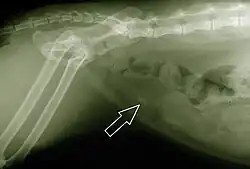

When symptoms indicate bladder stones, the first step is usually to take an x-ray. Most types of stones will appear readily in an x-ray, urate and occasionally cystine stones being the most common exceptions. Stones smaller than three millimeters may not be visible.[4] Ultrasonography is also useful for identifying bladder stones. Crystals identified in a urinalysis may help identify the stones, but analysis of the stones is necessary for identification of the complete chemical composition.